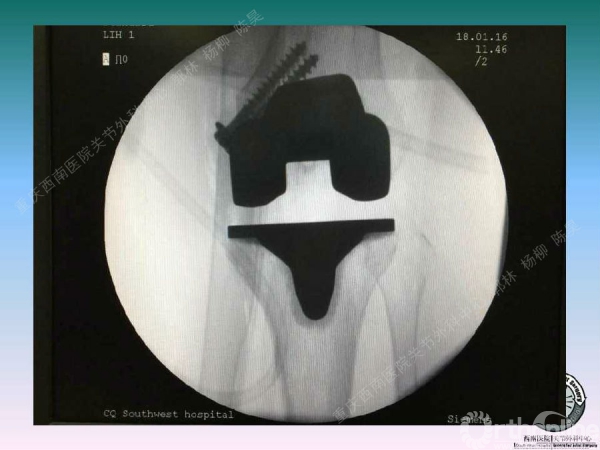

滑移截骨纠正关节外畸形

关节内滑移截骨的缺点和并发症